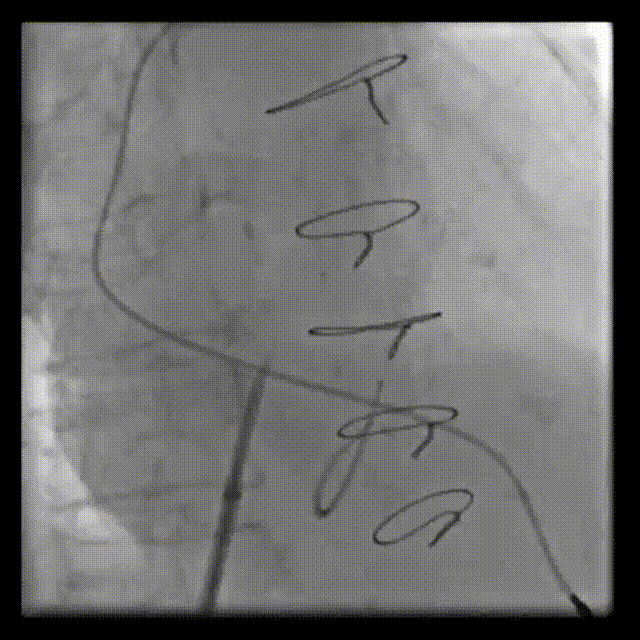

RAO:23° CRA:25°